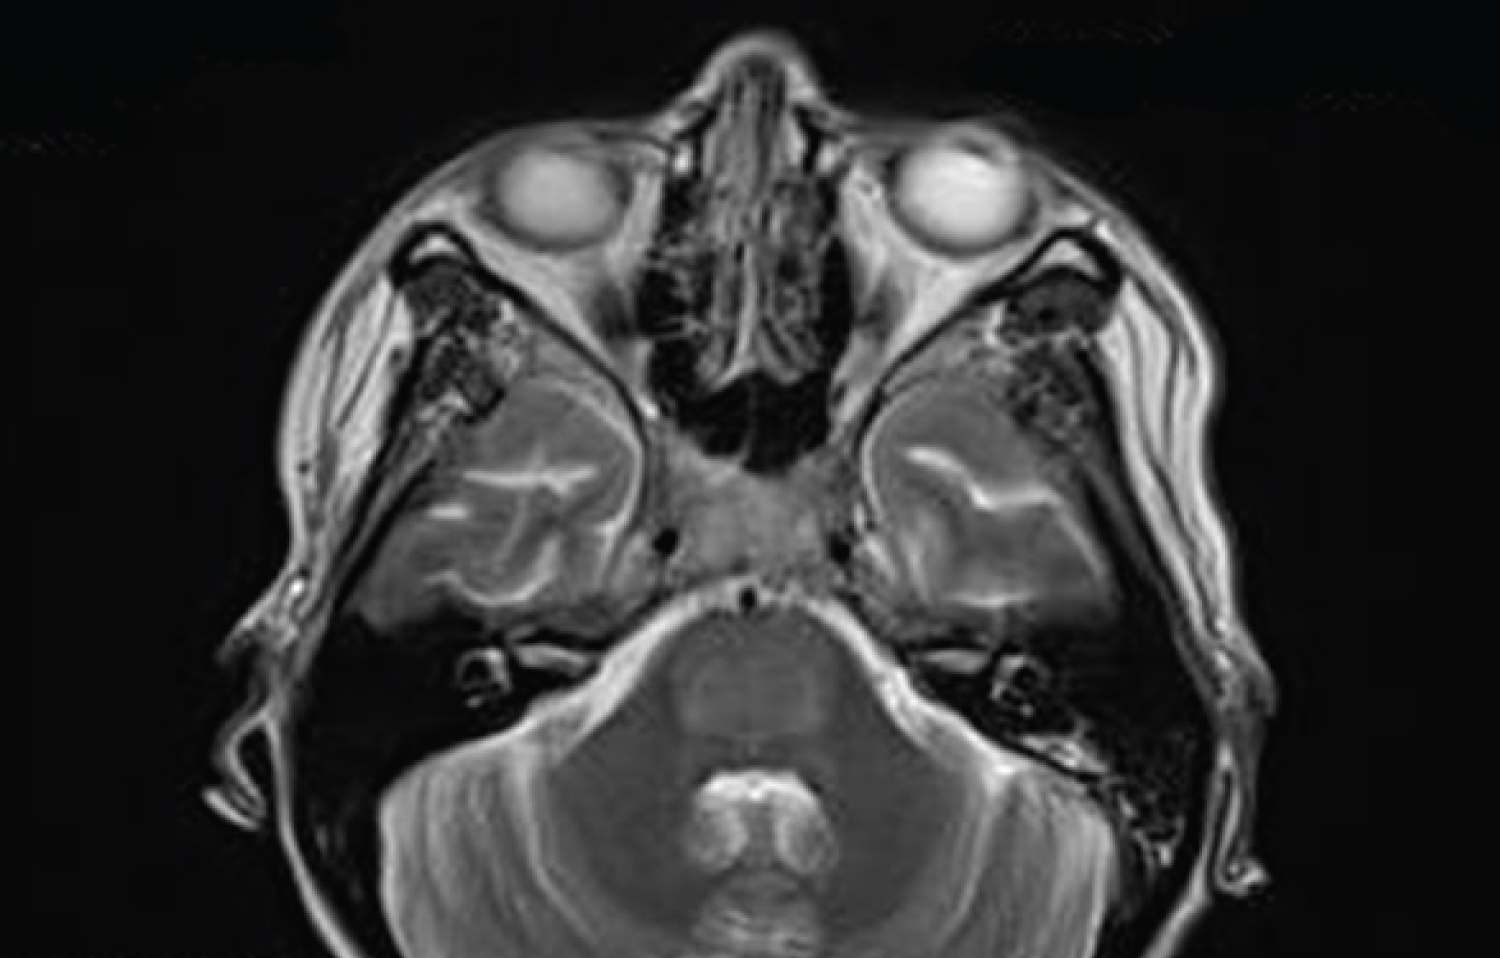

Five days after initial discharge, the patient was readmitted with ascending progressive weakness. On day one of her second admission, the patient on physical exam was alert and oriented, functionally capable of nodding her head yes or no, had full range of motion of her upper extremities with mildly reduced strength of 3/5, and notably in the lower extremities she had reduced strength 1/5 of her left foot and no movement in the right foot. By the second morning, she was alert but with sonorous respirations progressing to complete flaccid paralysis with aphasia. Brain MRI revealed restricted diffusion and FLAIR abnormality with increased signal in central pons and the superior medullary tectum with peripheral sparing suggesting osmotic myelinolysis syndrome (Figure 1).

Figure 1: Brain MRI hyperintensity of pons sparing periphery and corticospinal tracts on axial T2-weighted image View Figure 1